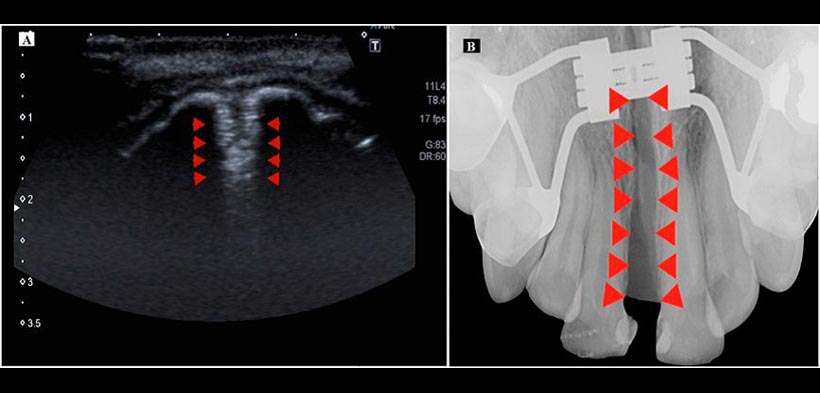

Figura 4. (A) Ecografía del maxilar superior durante la expansión, se observa la sutura palatina (puntas de las flechas). (B) Radiografía oclusal del maxilar superior, durante la expansión de la sutura palatina (puntas de las flechas).